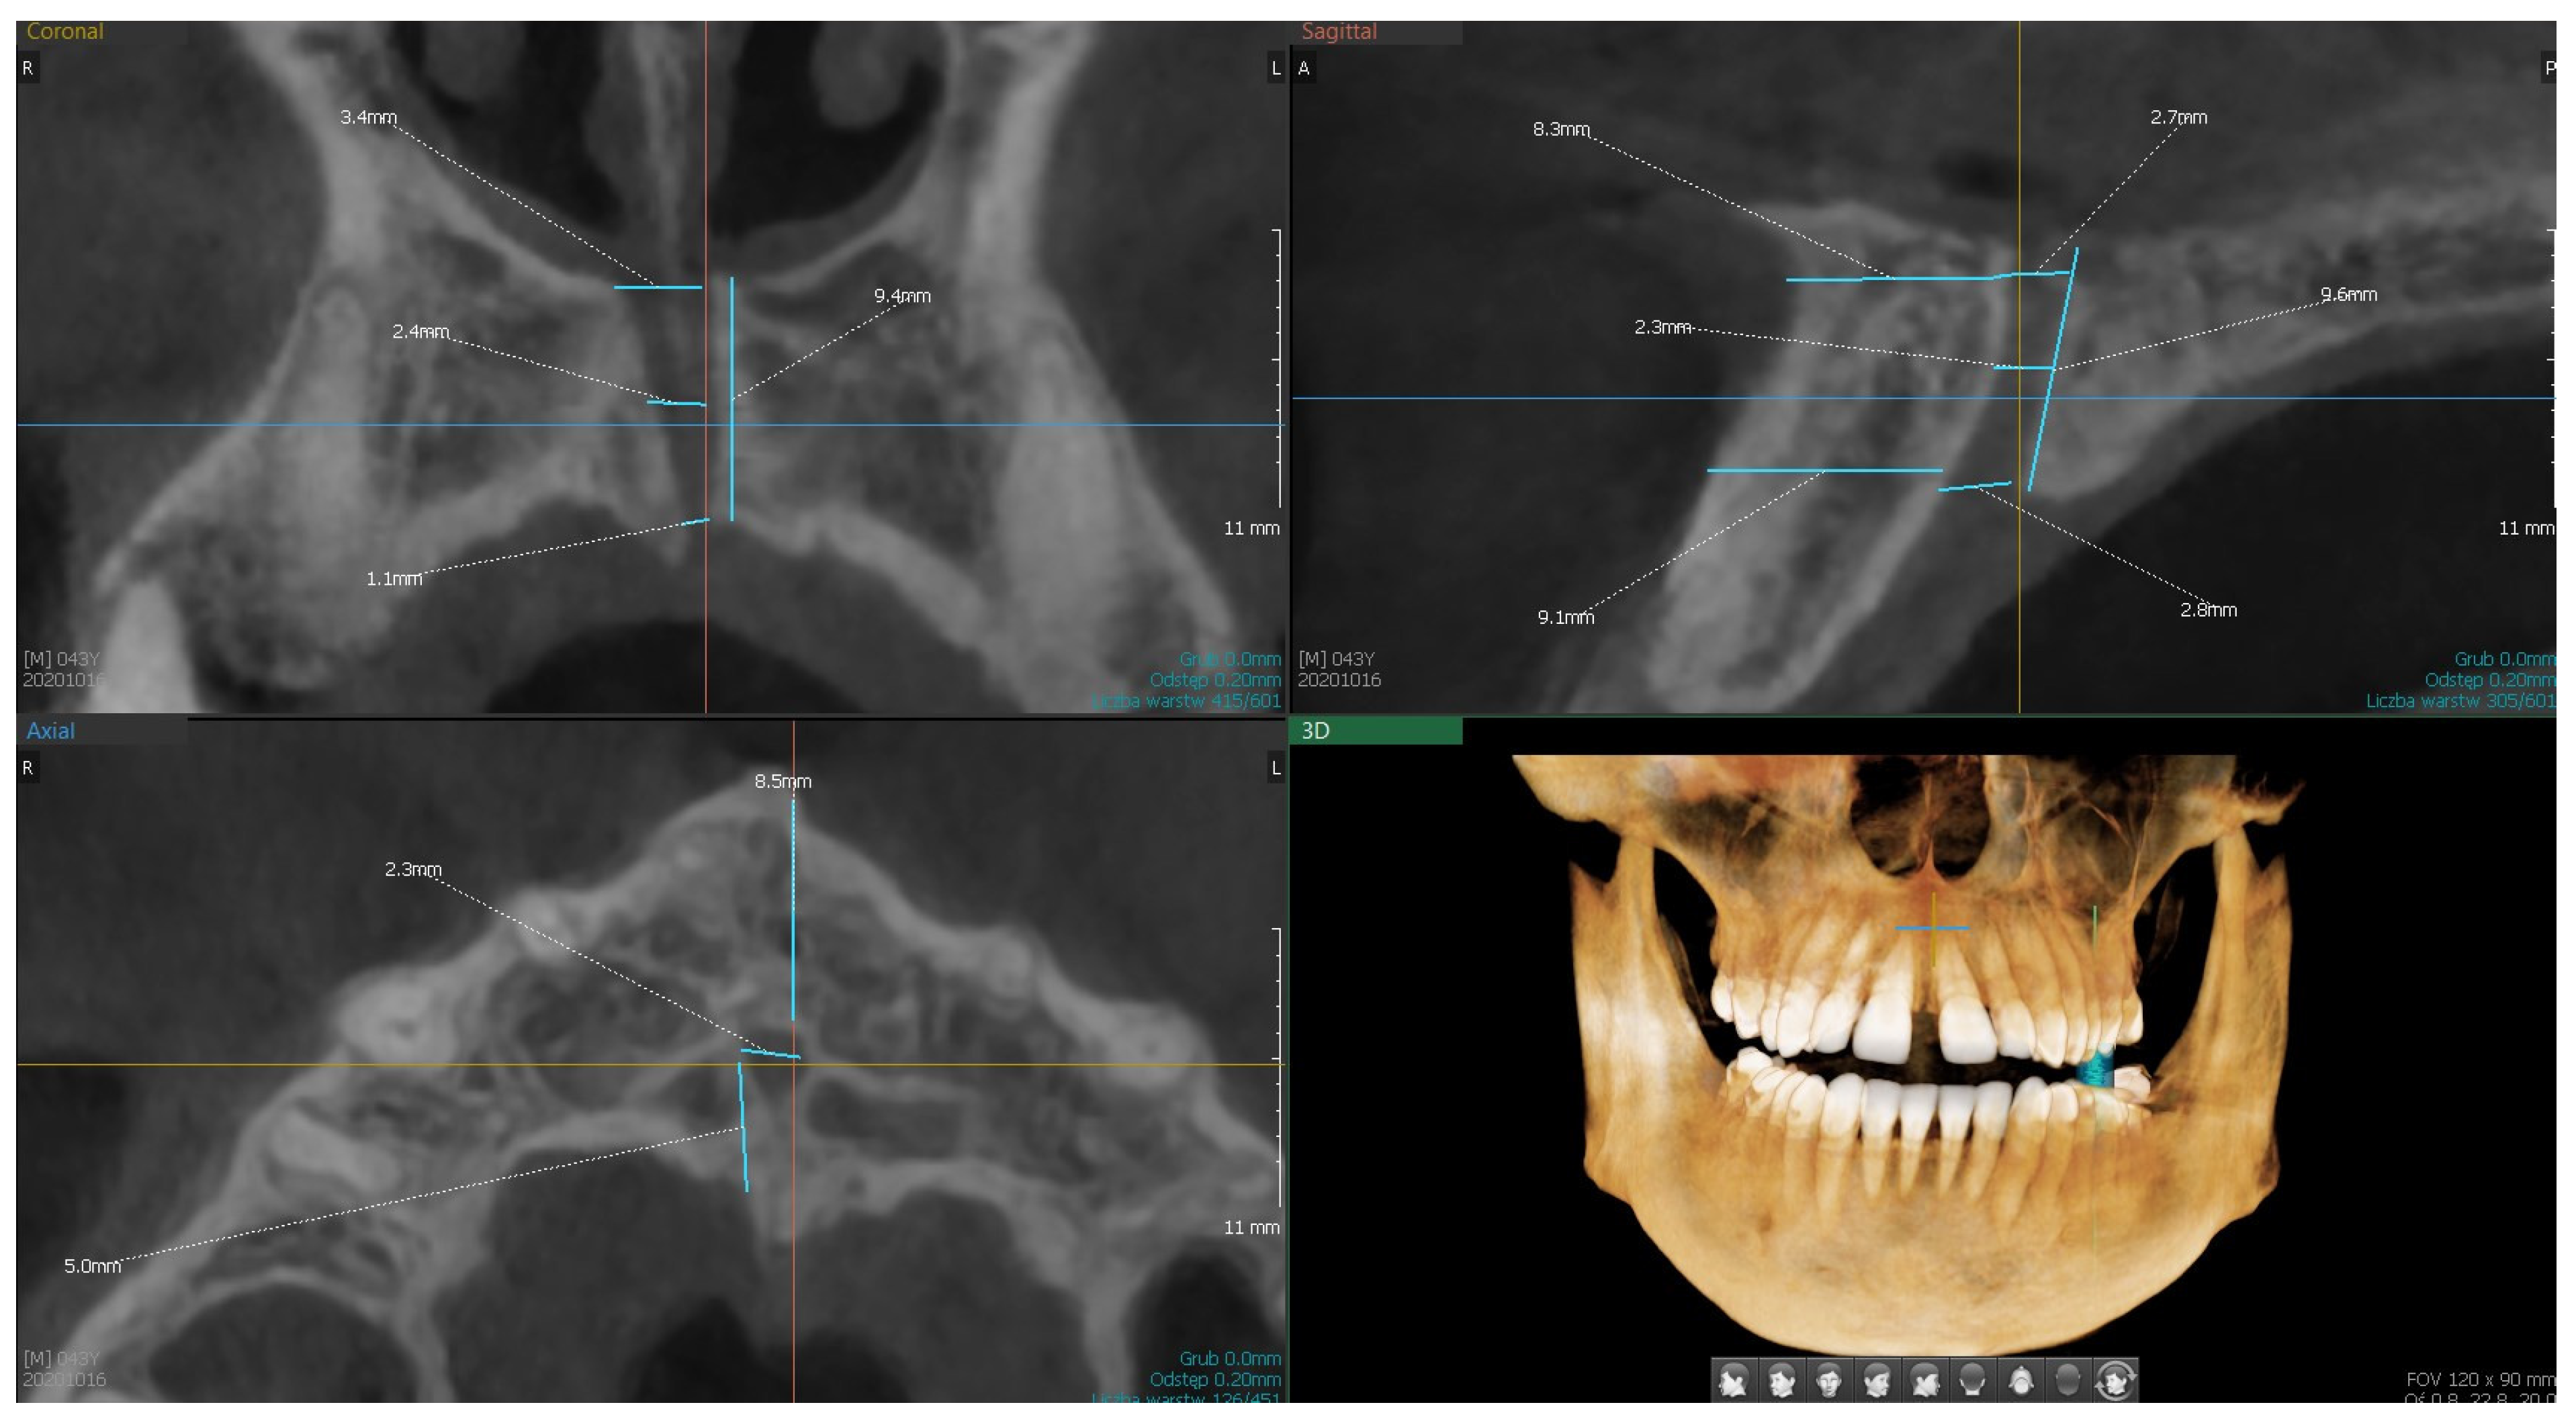

| Variable | Descriptive Statistics | |||||||

|---|---|---|---|---|---|---|---|---|

| Valid N | Mean | Median | Min | Max | Q1 | Q3 | SD | |

| S1.—length of the canal from the base of the nose to the palate | 150 | 9.67 | 9.60 | 4.00 | 16.60 | 8.00 | 11,20 | 2.47 |

| S2.—width of the canal at the base of the palate | 150 | 3.71 | 3.55 | 1.10 | 7.60 | 2.90 | 4.50 | 1.28 |

| S3.—width of the canal at the base of the nose | 149 | 3.30 | 3.00 | 0.90 | 6.90 | 2.30 | 4.20 | 1.29 |

| S4.—width of the canal in half-length | 150 | 2.62 | 2.50 | 0.80 | 6.70 | 1.60 | 3.30 | 1.14 |

| S5.—distance to the labial plate at the level of the mouth opening of the palatine canal | 150 | 6.66 | 6.75 | 2.00 | 11.30 | 5.70 | 7.70 | 1.73 |

| S6.—distance to the labial plate at the level of the nasal outlet | 149 | 9.31 | 9.10 | 4.80 | 14.40 | 8.00 | 10.90 | 2.15 |

| C1.—width of the canal at the base of the nose | 150 | 4.06 | 4.15 | 1.20 | 9.90 | 3.00 | 5.00 | 1.38 |

| C2.—width of the canal in half | 150 | 3.32 | 3.25 | 1.20 | 6.30 | 2.40 | 4.00 | 1.16 |

| C3.—width of the canal at the base of the palate | 150 | 3.87 | 3.70 | 1.10 | 9.20 | 2.60 | 5.00 | 1.54 |

| C4.—canal length | 150 | 10.27 | 10.10 | 1.00 | 21.10 | 7.70 | 12.70 | 3.52 |

| C5.—number of canals | 150 | 1.15 | 1.00 | 1.00 | 2.00 | 1.00 | 1.00 | 0.36 |

| A1.—number of openings | 150 | 1.09 | 1.00 | 1.00 | 3.00 | 1.00 | 1.00 | 0.31 |

| A2.—diameter of the main canal | 149 | 3.55 | 3.40 | 1.00 | 9.00 | 2.50 | 4.30 | 1.41 |

| A3.—distance to the palatal plate (bone thickness) | 150 | 3.57 | 3.30 | 0.60 | 7.80 | 2.40 | 4.70 | 1.55 |

| A4.—distance to the labial plate | 150 | 6.49 | 6.45 | 1.40 | 10.40 | 5.40 | 7.50 | 1.78 |